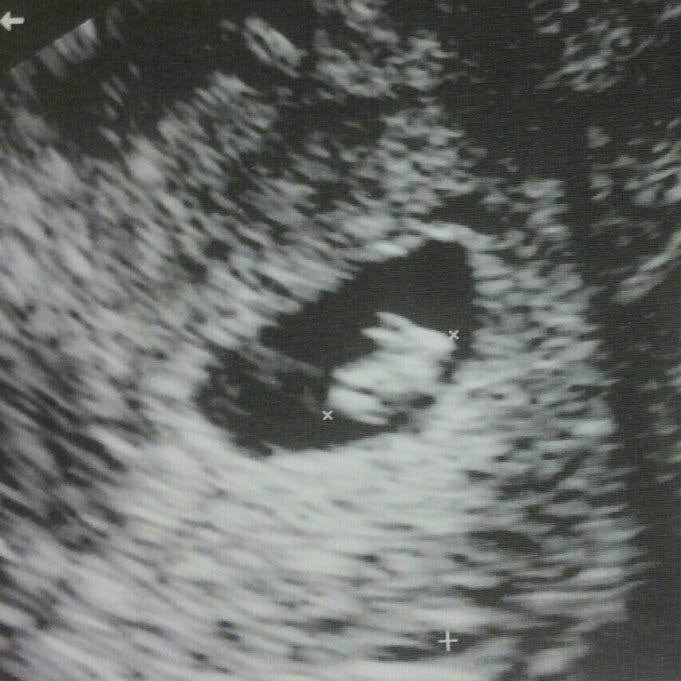

For nu venter parret deres fjerde barn – og det var sågar den kommende far til fire, der opdagede ”babybulen” hos sin nu gravide kæreste.

Alt sammen var noget, som Rachel døjede med, mens hun ventede parrets tre andre børn. Og det fik Tim til at spekulere: Kunne hun på mystisk vis være gravid igen? Og kunne Tim alligevel være faderen, selv om han i realiteten ikke burde kunne gøre sin kæreste gravid?

Og ja… herefter kunne han så hurtig konstatere, at den var god nok. Rachel var gravid!